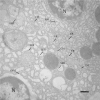

Aeromonas bacteria can cause an infection characterized by septicemia and is one of the most common pathogens in tropical fish. This disease is responsible for high morbidity and mortality rates, causing considerable losses in aquaculture. Thus, the understanding of its pathophysiology is crucial to develop control strategies of this bacterial infection in farmed fish. This study aimed to characterize early pathological aspects of acute sepsis in pacu (Piaractus mesopotamicus) experimentally infected with Aeromonas hydrophila. A total of 160 juvenile pacus were inoculated intraperitoneally with A. hydrophila (1.78 x 109 CFU/mL) and at 0 (control), 1, 3, 6, and 9 hours post-inoculation (hpi), animals were anesthetized and samples were collected for microbiological, light microscopy and transmission electron microscopy (TEM) analyzes. The results showed the occurrence of hemodynamic alterations, such as hemorrhage and congestion, which were observed mainly after 6 and 9 hpi. It was possible to re-isolate Aeromonas at all sampling times except in control group. However, just after 9 hpi it was possible to find the bacteria in all fish and tissues. Light microscopy analyses revealed a degenerative process, necrosis and vascular damage mainly at 6 and 9 hpi. According to the ultrastructural examination, areas of cellular death were identified in all examined tissues, especially at 6 and 9 hpi. However, the most severe, related to necrosis, were observed after 6 and 9 hpi. The findings suggested that this bacterium spreads in the first hpi through the fish organs, mainly affecting spleen, liver and kidney, causing irreversible lesions at the molecular level.